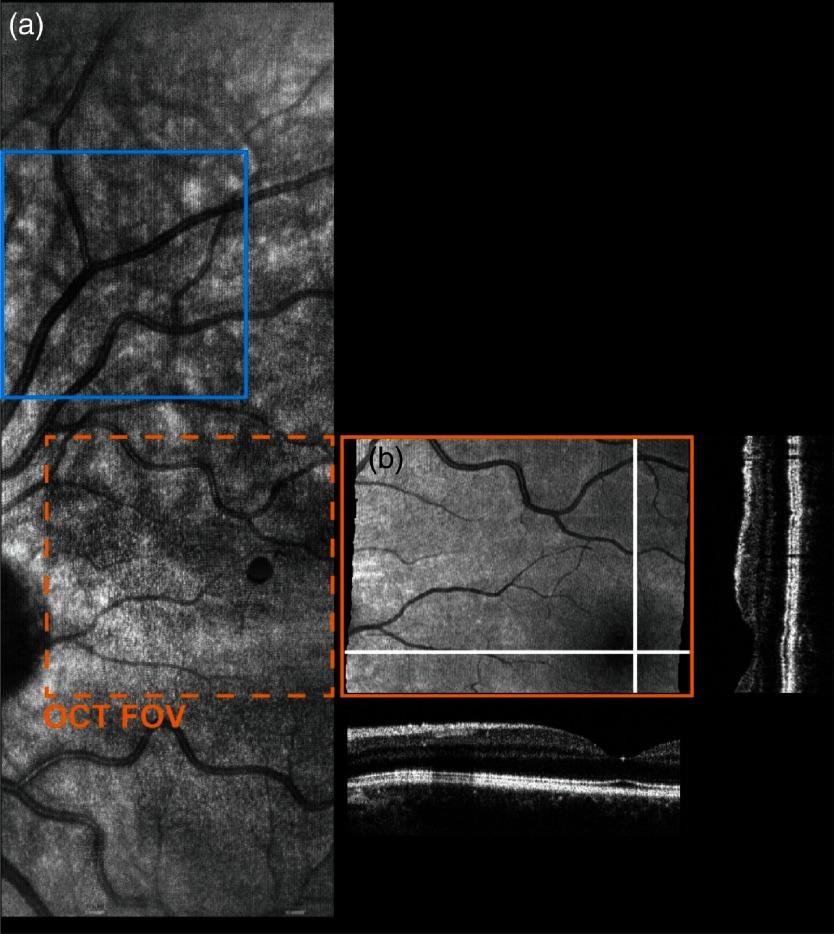

Optical coherence tomography (OCT) is the gold standard for quantitative ophthalmic imaging. The majority of commercial and research systems require patients to fixate and be imaged in a seated upright position, which limits the ability to perform ophthalmic imaging in bedridden or pediatric patients. Handheld OCT devices overcome this limitation, but image quality often suffers due to a lack of real-time aiming and patient eye and photographer motion. We describe a handheld spectrally encoded coherence tomography and reflectometry (SECTR) system that enables simultaneous reflectance and cross-sectional OCT imaging. The handheld probe utilizes a custom double-pass scan lens for fully telecentric OCT scanning with a compact optomechanical design and a rapid-prototyped enclosure to reduce the overall system size and weight. We also introduce a variable velocity scan waveform that allows for simultaneous acquisition of densely sampled OCT angiography (OCTA) volumes and widefield reflectance images, which enables high-resolution vascular imaging with precision motion-tracking for volumetric motion correction and multivolumetric mosaicking. Finally, we demonstrate human retinal OCT and OCT angiography (OCTA) imaging using handheld SECTR on a healthy volunteer. Clinical translation of handheld SECTR will allow for high-speed, motion-corrected widefield OCT and OCTA imaging in bedridden and pediatric patients who may benefit ophthalmic disease diagnosis and monitoring.

光学相干断层扫描(OCT)是眼科定量成像的金标准。大多数商业和研究系统要求患者固定并以坐姿直立进行成像,这限制了对卧床或儿科患者进行眼科成像的能力。手持式OCT设备克服了这一限制,但由于缺乏实时瞄准以及患者眼睛和摄影师的移动,图像质量往往会受到影响。我们描述了一种手持式光谱编码相干断层扫描和反射测量(SECTR)系统,该系统能够同时进行反射率和横截面OCT成像。手持式探头采用定制的双程扫描透镜,用于全远心OCT扫描,具有紧凑的光机械设计和快速成型的外壳,以减小整个系统的尺寸和重量。我们还引入了可变速度扫描波形,可同时采集密集采样的OCT血管造影(OCTA)容积和宽视野反射率图像,从而实现高分辨率血管成像,并通过精确的运动跟踪进行容积运动校正和多容积拼接。最后,我们展示了在一名健康志愿者身上使用手持式SECTR进行的人体视网膜OCT和OCT血管造影(OCTA)成像。手持式SECTR的临床应用将允许对卧床和儿科患者进行高速、运动校正的宽视野OCT和OCTA成像,这可能有助于眼科疾病的诊断和监测。